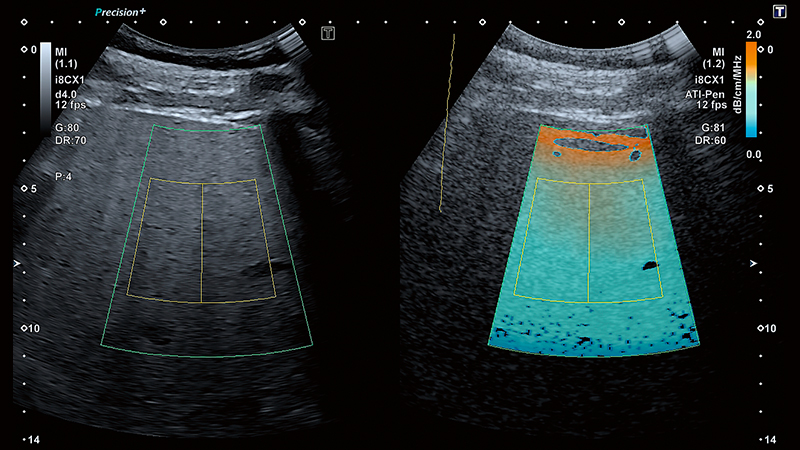

Візуалізація загасання (ATI) — це інноваційний інструмент, який може допомогти клініцистам в оцінці ступеня стеатозу. Рання характеристика наявного стеатозу є важливою як для надійного прогнозу, так і для ефективної терапії. ATI забезпечує кольорове кодування коефіцієнта загасання в тканинах печінки залежно від частоти.

ATI та SWE можна оцінювати одночасно за допомогою одного сканування. Завдяки цьому клініцисти можуть оцінити стеатоз печінки та фіброз ще швидше та ефективніше.